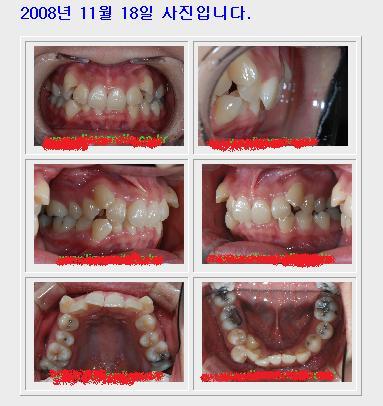

쫌 있다가 나의 교정치료모습이 담긴 치아사진을 보면 알겠지만,

처음 찍은 사진은 꺼멍이 투성이지만, 나중에 어금니를 보면 금으로 때워져있는 걸 볼 수 있음ㅋㅋ

이건 사랑니뽑기로 했던 병원에서 소개시켜줘서 갔을 때가 저 날짜였음.

우리집도 풍족한 집안이 아닌지라 바로 시작할 수 없음 + 교정하면 맛난걸 많이 못먹으니까 하기전에 뒈지게 먹고 하자 그런 맘에 진료는 2008년도에 진단받고, 시작하기는 2009년 5월에 시작함.

내가 저런식이였다니.. 덧니보면서 충격먹었음.

그래도 좀 입술이 붙어있는 사진은 저런게 아니였는데,

거울을 본 내 모습은 저런 모습이 아니였는데..

거죽 없앤 사진은 그냥 처참함..ㅜㅜ